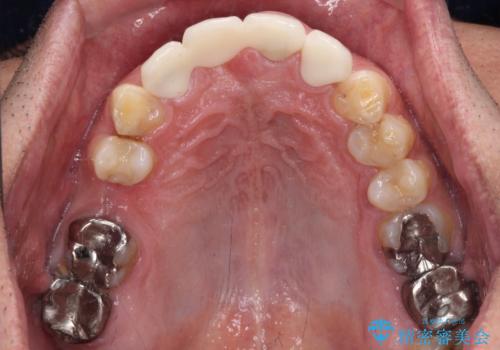

歯肉移植や根管治療終了後、オールセラミッククラウンおよびブリッジにて補綴することとしました。

歯の幅径のバランスが取れ、自然な口元となりました。